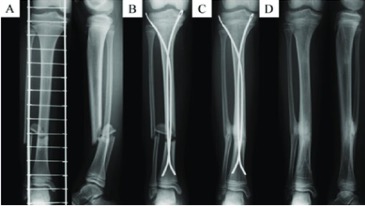

Figs. 1-A through 1-D Radiographs of a 4-year-old girl who had sustained a short spiral tibial shaft fracture while skiing.

Figs. 1-A and 1-B The patient was treated with gentle closed reduction and long leg cast immobilization.

Figs. 1-C and 1-D The patient subsequently progressed to healing in anatomic alignment.